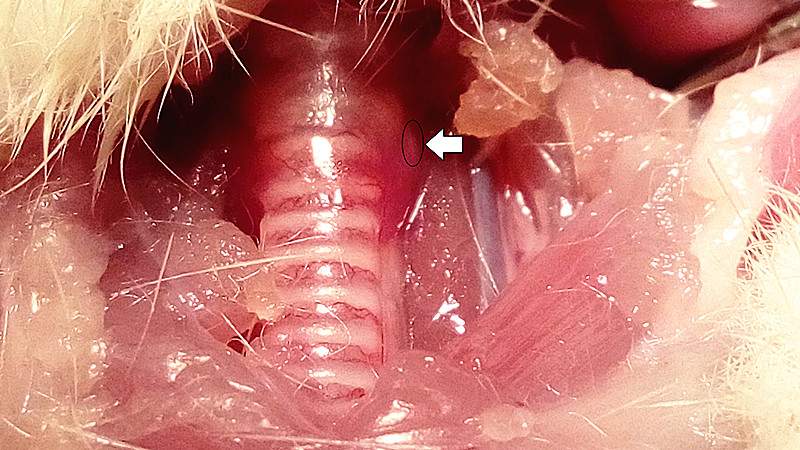

最近做大鼠甲状旁腺原代培养,参考文献也无法准确定位,请问有没有老师做过,可以发一下切下的甲状旁腺的图片,下面是我取得甲状旁腺的部位,以及HE染色的结果,请各位老师看看是不是甲状旁腺组织。 IMG_20160412_160606_副本.jpg jzpx hs 2_副本.jpg |